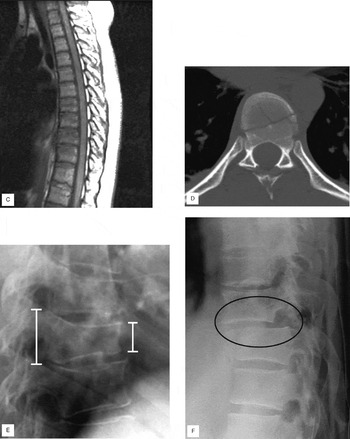

Eagle-449: A volumetric, whole-brain compilation of brain, MRI showing cord compression due to anterior translation of,

MRI showing cord compression due to anterior translation of, Netter's Correlative Imaging: Neuroanatomy: with,

CT & MRI Pathology: A Pocket Atlas, Third Edition, Delayed diagnosis of a fractured anterior arch of the atlas,

Delayed diagnosis of a fractured anterior arch of the atlas, Pediatric Trauma Computed Tomography: A Comprehensive Guide,

MRI Anatomy | SpringerLink, Spinal Injuries (Chapter 7) - Color Atlas of Emergency Trauma

Spinal Injuries (Chapter 7) - Color Atlas of Emergency Trauma